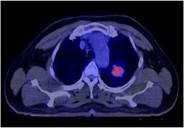

Để chẩn đoán xác định giai đoạn và lập kế hoạch điều trị một cách chính xác hơn, bệnh nhân đã được chỉ định chụp PET/CT (có chỉ định mô phỏng để lập kế hoạch xạ trị).

Hình 3: Hình ảnh chụp PET/CT: có khối u thuỳ trên phổi trái với kích thước 2x3cm,

tăng hấp thu F18-FDG không đều, max SUV=6,89. Hạch thượng đòn trái kích thước 0,6x0,7cm.

Chẩn đoán xác định: Ung thư thuỳ trên phổi trái (ung thư biểu mô tuyến), T2N3Mo (Giai đoạn IIIB trên bênh nhân có đợt cấp gút mạn tính).